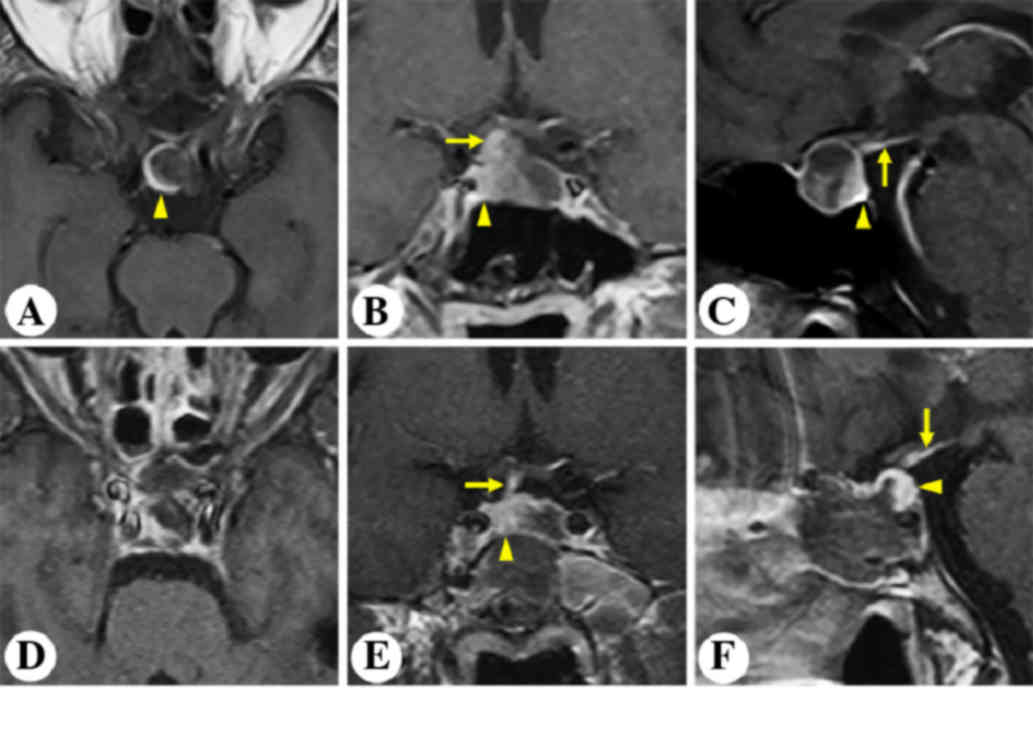

A 63-year-old male complained of severe intermittent headache for the past three years. MRI revealed an intrasellar non-enhancing lesion (Fig. 1). The pituitary gland and stalk was stretched and displaced posterolaterally to the right (Fig. 1A-C). The patient underwent microscopic transphenoidal surgery (Fig. 2). Postoperative MRI demonstrated gross-total resection of the tumor and an anatomically intact gland and stalk (Fig. 1D-F). An intraoperative view of the pituitary gland (Fig. 2) is shown in Fig. 2A after tumor removal.

Figure 1.

Patient 1. Representative post contrast T1-weighted images. Preoperative (A) horizontal, (B) coronal and (C) sagittal MRI images demonstrated the space-occupying lesion in the sellar region. Postoperative (D) horizontal, (E) coronal and (F) sagittal MRI images showed gross-total resection of the tumor and the anatomically intact pituitary stalk and gland. Arrows indicate the pituitary stalk. Arrowheads indicate the pituitary gland. MRI, magnetic resonance imaging.